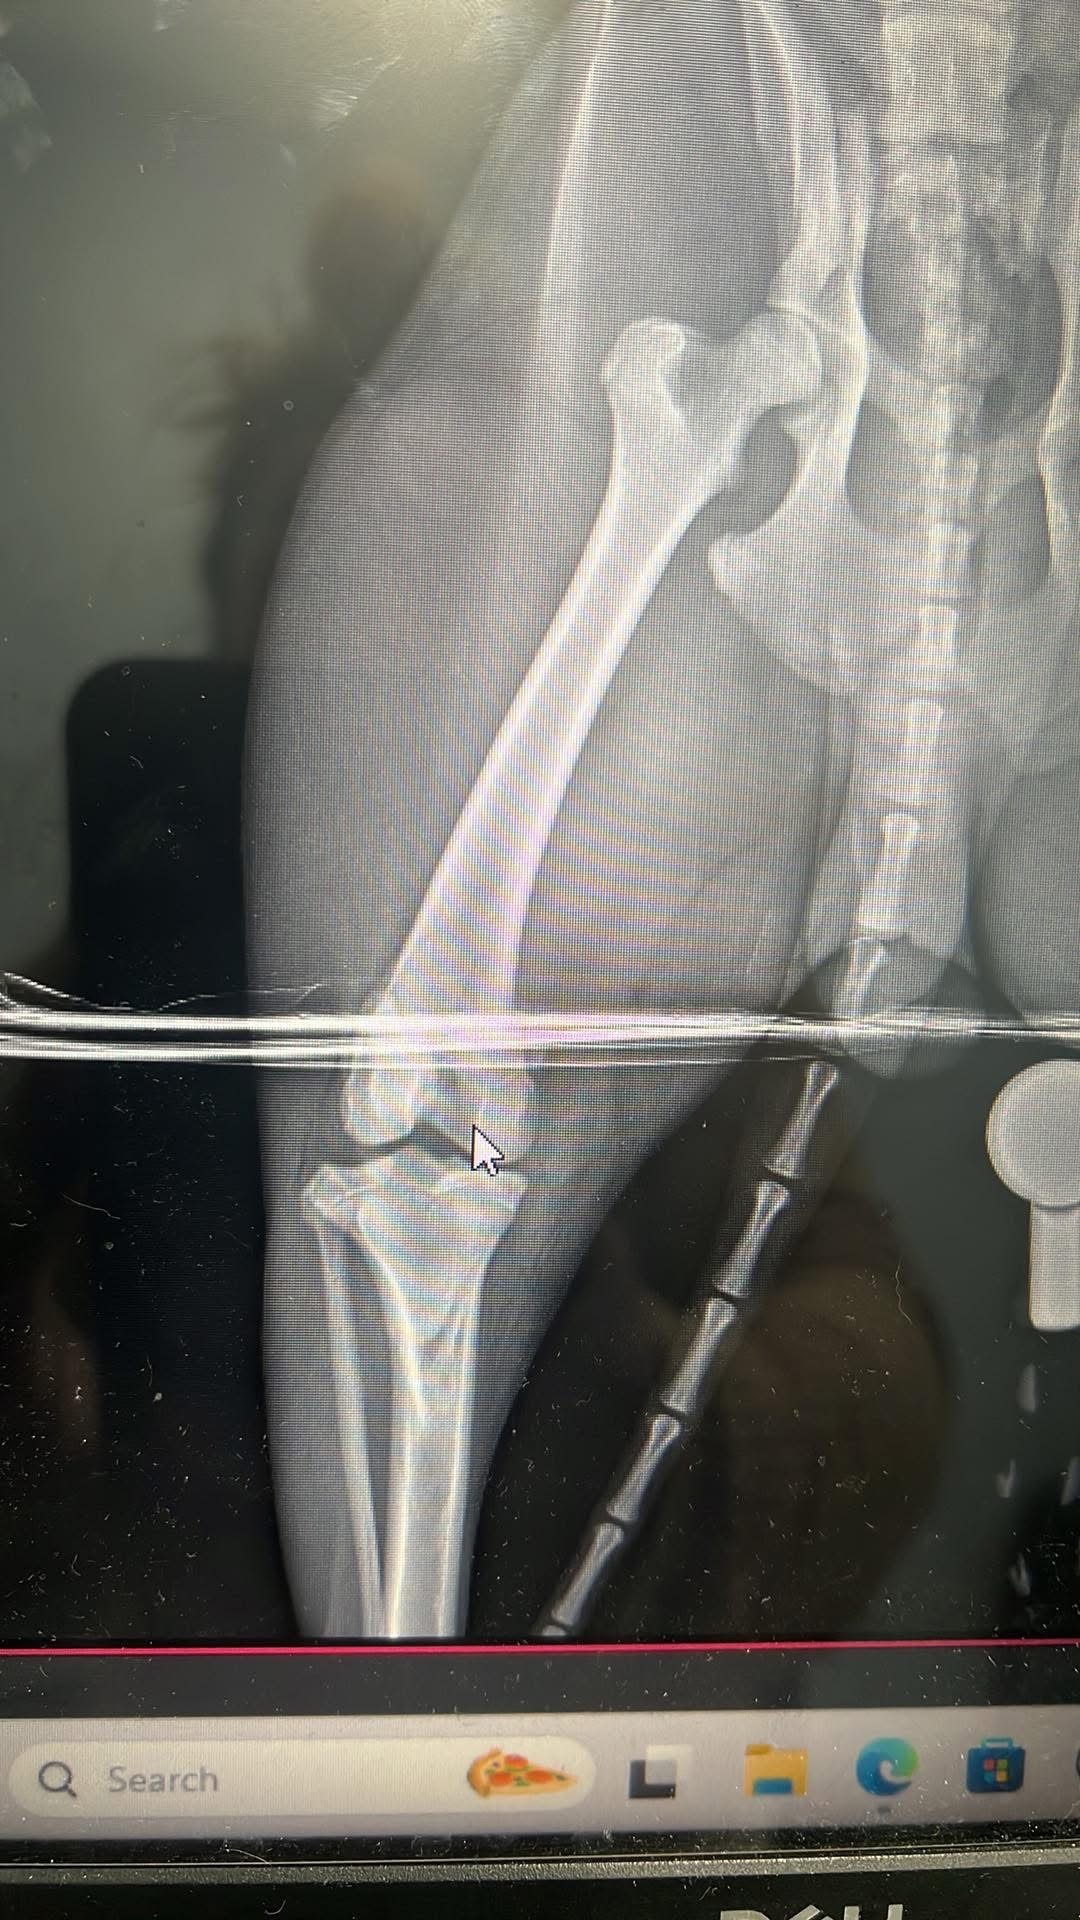

Toby has been with us since the day he was born, and he’s truly the sweetest, most gentle dog I’ve ever known. He’s a big part of our family, always bringing us joy and comfort. Recently, Toby managed to escape and was tragically hit by a car. The accident left him unable to walk, with a broken hip and two broken back legs. Watching him try his best to get up and move, despite the pain, is heartbreaking. He’s fighting so hard, and it’s clear he wants nothing more than to be back on his feet, playing and cuddling with us again.

Toby’s only chance at recovery is emergency surgery. Without it, he won’t be able to walk or enjoy the life he loves. The cost of the surgery is overwhelming for us, and we can’t imagine losing him when he’s trying so hard to stay strong. We’re reaching out to our community for help because we believe in the kindness of others and the power of coming together in tough times.

Toby’s only chance at recovery is emergency surgery. Without it, he won’t be able to walk or enjoy the life he loves. The cost of the surgery is overwhelming for us, and we can’t imagine losing him when he’s trying so hard to stay strong. We’re reaching out to our community for help because we believe in the kindness of others and the power of coming together in tough times.